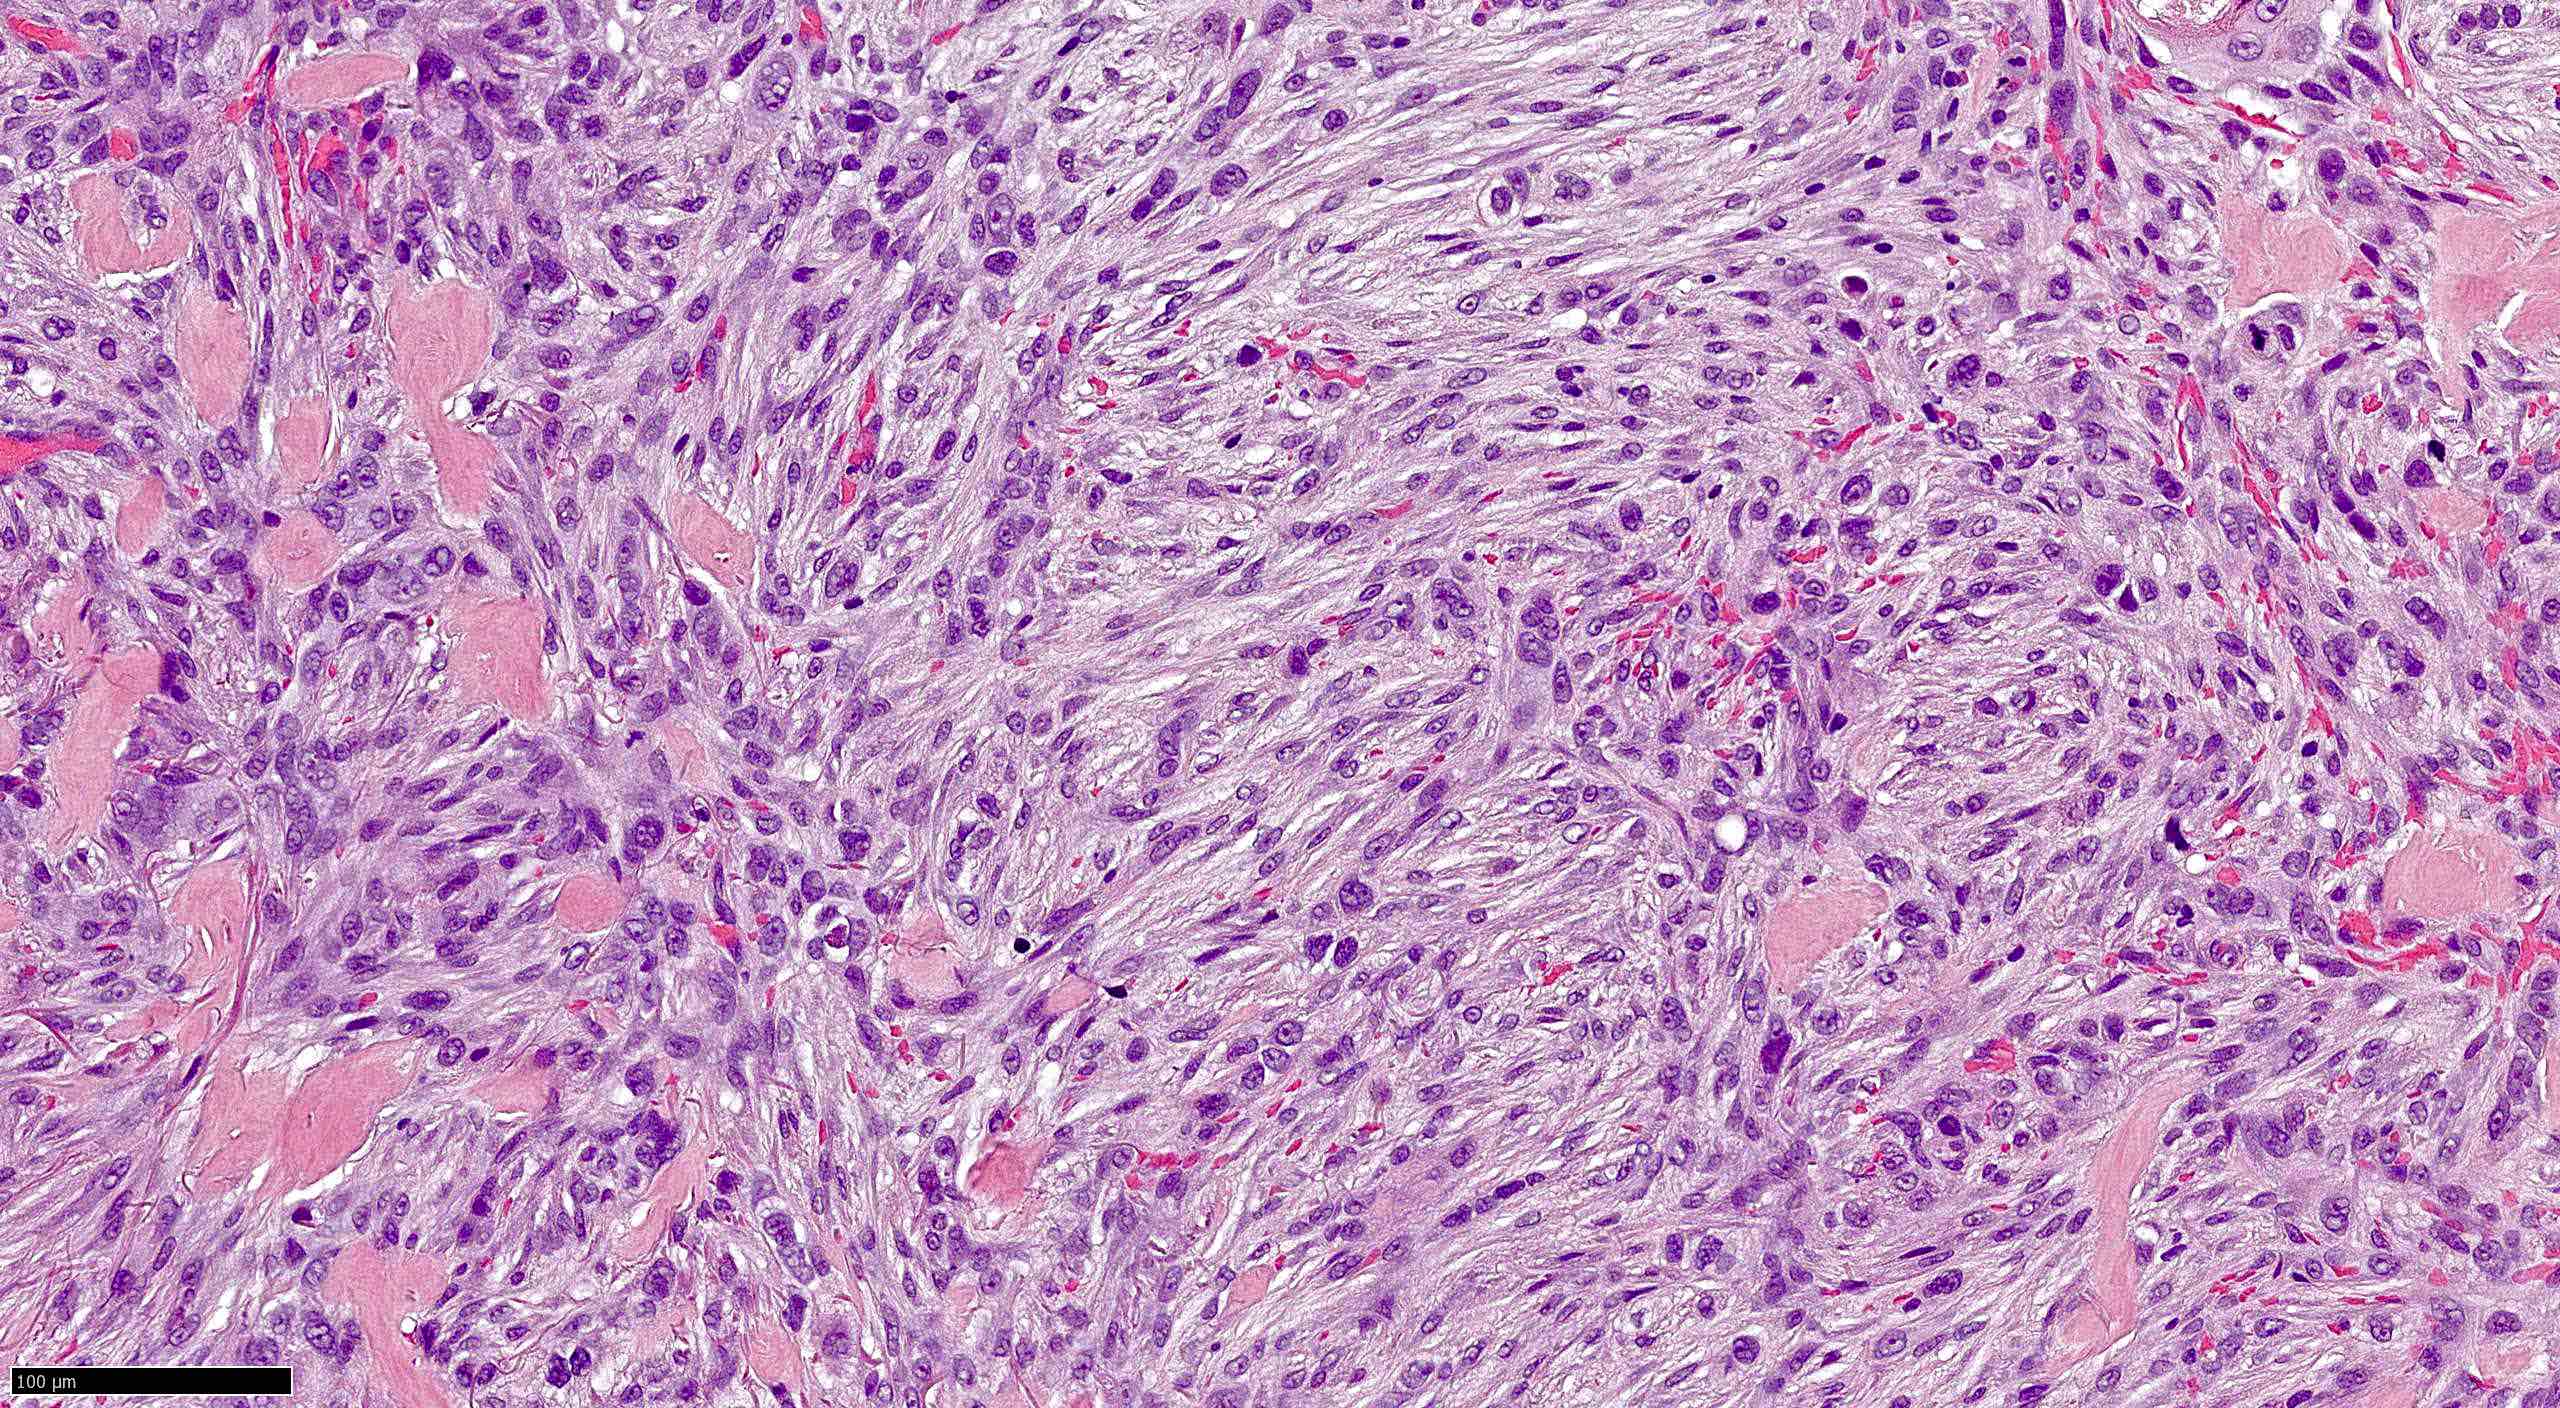

Common variants (Calonje: McKee's Pathology of the Skin, 5th Edition, 2019)

- Morpheaform (sclerosing, morphoeic) BCC

- Thin strands and nests of basaloid cells

- Limited peripheral palisading

- Stroma is dense and sclerotic

- Extensive spread

- Perineural invasion can be seen

Microscopic (histologic) images

Contributed by Antonina Kalmykova, M.D., Phillip H. McKee, M.D., Sate Hamza, M.D., Eduardo Calonje, M.D.,

Wayne Grayson, M.B.Ch.B., Ph.D., James Sampson, M.B.B.S., M.Sc. and Assia Bassarova, M.D., Ph.D.